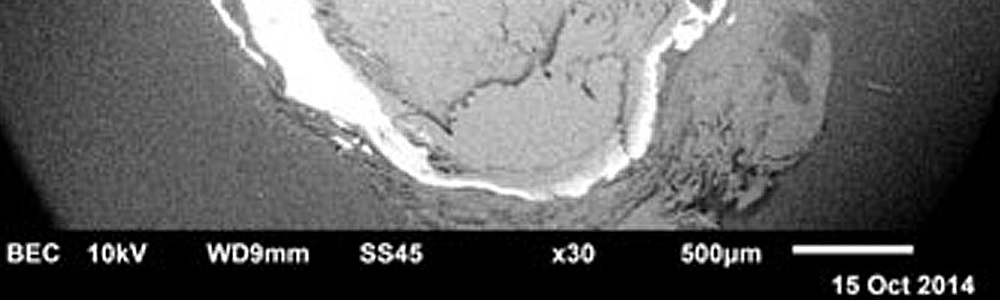

“There doesn't seem to be any immune cells (white blood cells) present anywhere. ... Pathology on a fibrotic capsule this old is extremely rare. I have nothing to compare your sample with.”

- University lab report after Haematoxylin and Eosin tissue stains, November 2014

Reposted May 17, 2022 - December 23, 2014  Albuquerque, New Mexico - Continuing with what was learned after use of Haematoxylin and Eosin to stain tissue sections of the object removed from Natalie's upper right arm. Photomicrographs and graphics are provided by university laboratory. Images on videotape by Sid Goldberg, Toronto TV director and investigator.

Reposted May 15, 2022 - December 21, 2014  Albuquerque, New Mexico - Continuing with what was learned about material and elemental composition of the object removed from Natalie's upper right arm using SEM/EDS, which is Scanning Electron Microscopy and Energy Dispersive Spectroscopy X-ray microanalysis. Images are laboratory investigation on videotape by Sid Goldberg, Toronto TV director and investigator. Graphics and photomicrographs are provided by university laboratory.